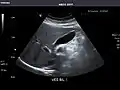

Abdominal Ultrasound (Full Exam)

STRUCTURED REPORT

(Technique: Transabdominal ultrasonography; Device: Toshiba Aplio XG)

Liver: Diffusely homogeneous and normal in echogenicity. No focal mass or contour nodularity. No intrahepatic biliary ductal dilatation.

Portal Vein: Patent main portal vein.

Gallbladder: No stones, wall thickening, or pericholecystic fluid.

Common Bile Duct: Nondilated measuring 1.3 mm at the level of the porta hepatis.

Pancreas: Visualized portions unremarkable.

Spleen: Normal in size.

Kidneys: Right and left kidneys measure 11.5 cm and 12 cm in length respectively. No hydronephrosis. Small left lower pole kidney cyst.

Ascites: None.

Aorta: Visualized portions normal in caliber, 16 x 15 mm.

IVC: Normal.

IMPRESSION:

Normal abdominal ultrasound.